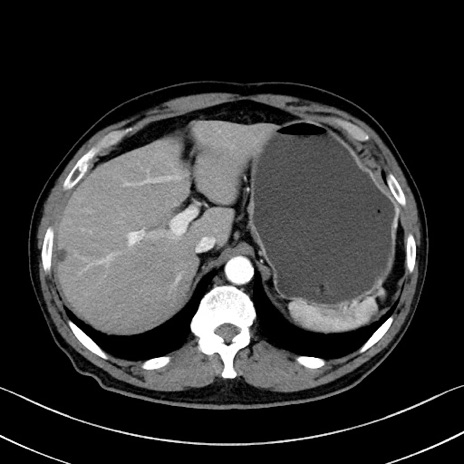

症例35(横断像)

【症例】70歳代 男性

【主訴】腹部膨満、嘔吐

【現病歴】昨日より腹部膨満感出現。本日増悪し、仙痛出現。嘔吐あり、受診。

【既往歴】糖尿病、胆摘後

【身体所見】BP 149/80mmHg、HR 74/min、BT 35.9℃、腹部:膨満、軟、圧痛なし。腸雑音減弱あり。上腹部正中切開瘢痕あり。

【データ】WBC 13500、CRP 1.72